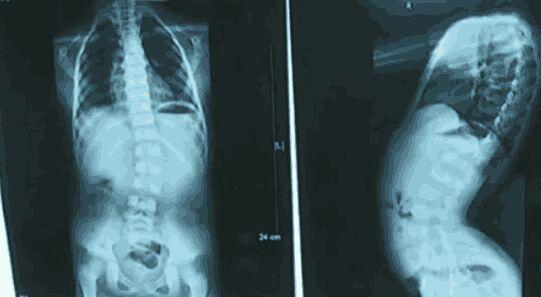

Tuy nhiên, khi nhận được kết quả phim chụp X-quang từ bác sĩ, người mẹ đã không khỏi bàng hoàng. Hình ảnh cho thấy cột sống của con gái chị bị cong vẹo đến nỗi khó tin. Bác sĩ cho biết nguyên nhân dẫn đến tình trạng cong vẹo cột sống, có thể liên quan đến tư thế ngồi sai trong thời gian dài của trẻ.

Nếu tình trạng này được phát hiện sớm hơn, và tư thế ngồi của bé được điều chỉnh kịp thời thì có thể đã không cần phải phẫu thuật để chỉnh lại cột sống như hiện tại. Nghe bác sĩ kết luận, người mẹ ôm mặt bật khóc, hối hận vì đã lơ là, không quan tâm quan sát con nhiều hơn để chuyện không may này xảy ra với đứa trẻ.